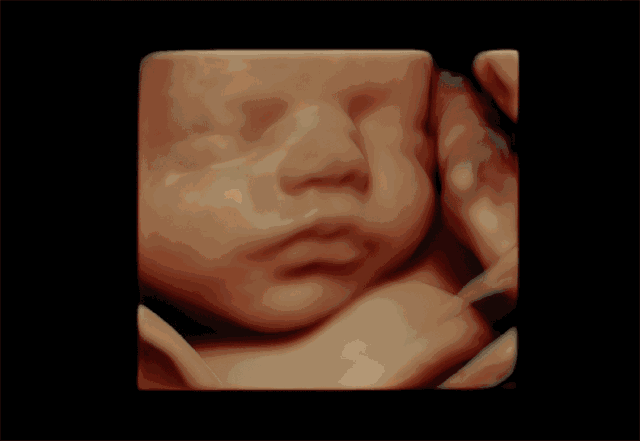

孕婦彩超是一種超聲檢查。除了一般的彩色超聲波功能外,還可以執(zhí)行胎兒頭部和臉部的立體成像。它可以清楚地顯示眼睛、鼻子、嘴巴、腹等狀況,并可以幫助醫(yī)生直接診斷胎兒先天性畸形,包括表面畸形,內(nèi)臟畸形和面部和面部畸形,可以確定胎兒在子宮中的確切位置。

四維彩色多普勒超聲在功能的基礎(chǔ)上還增加了時間維度參數(shù),并且可以實時觀察胎兒動態(tài)的運動圖像,能夠更加清晰的篩查胎兒在子宮內(nèi)的狀態(tài),篩查胎兒是否有異常,提供準確的科學依據(jù),及早發(fā)現(xiàn)、及早作出解決方案。

彩超是能夠監(jiān)測到胎寶寶的健康情況,其中四維彩超除了是準媽媽和BB的“第一次”見面,還能夠看到ta在肚子里或活潑或文靜的可愛模樣,從而進行重要的排畸檢查,所以也叫胎兒畸形篩查,是孕期特別重要的一次超聲檢查。

飛利浦EPIQ7高端四維彩超擁有高品質(zhì)自動成像分析技術(shù),它可以全方位,多角度地觀察宮內(nèi)胎兒的生長發(fā)育情況,為早期診斷胎兒先天性畸形,如唇裂、脊柱裂、顱腦發(fā)育異常、骨骼發(fā)育異常、心血管畸形等提供準確的科學依據(jù)。